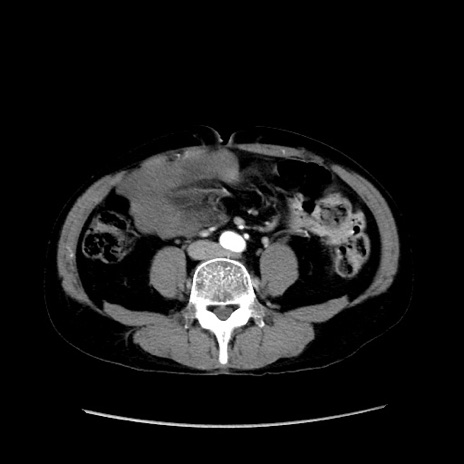

症例37(横断像)

【症例】40歳代 男性

【主訴】腹痛

【現病歴】4時間ほど前に電車に乗車中に臍部上より腹痛出現。徐々に増悪し起立困難となり、救急外来受診。生ものは数日食べていない。今朝お雑煮を食べた。

【身体所見】BT 36.8℃、BP 117/84mmHg、HR 91/min、SpO2 97%、苦悶様、腹部:臍上部広範囲圧痛あり、反跳痛±

【データ】WBC 8100、CRP 0.03